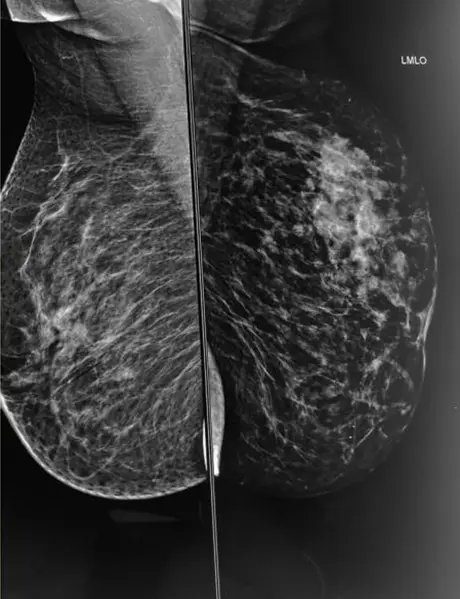

Left breast CC and MLO views

A) & B) Left breast CC and MLO view showing large asymmetric density in upper and central quadrant of left breast (black arrows) with associated interstitial thickening (white arrow) and architectural distortion .Multiple mass like areas seen in the medial and lower quadrant (red arrows) of left breast

A) & B) Large area of abnormality in upper half of left breast with dominant central mass (straight white arrow). Multiple dilated and thickened ducts (straight red arrow)are seen extending from the mass.

C) Multiple lymph nodes (curved white arrow) with thickened cortices in left axilla